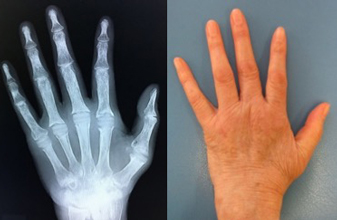

2. 手指の外傷

手指の小さい骨の骨折においては初期治療が極めて重要です。手術が必要かどうかの見極めが時に難しく、専門医のもとを受診され治療方針を決定することをおすすめします。当院では外傷の程度や患者の年齢、社会背景なども考慮し手術も含めた最善の方法を選択しています。手術時に用いる器械は手指に特化した特殊なものを用いて、より正確な整復を心がけています。